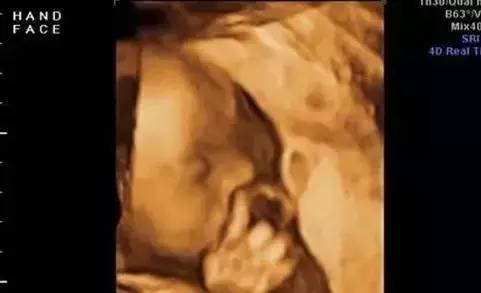

最近一张在妈妈肚子里的老司机的图片红遍网络,被点击百万次,是的,这位老司机竟然在妈妈肚子里完成了开车的标准动作,简直把小派笑晕了,这就是传说中的自带技能的神奇bab...

最近一张在妈妈肚子里的“老司机”的图片红遍网络,被点击百万次,是的,这位“老司机”竟然在妈妈肚子里完成了开车的标准动作,简直把小派笑晕了,这就是传说中的自带技能的神奇baby吗?